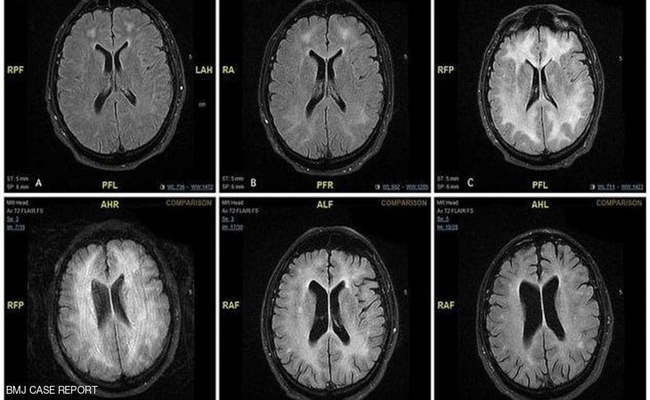

صورة شعاعية تكشف ما يفعله الكوكايين بالدماغ

كشفت صور أشعة مقطعية على المخ، الضرر الذي يصيب الدماغ جراء تعاطي مادة الكوكايين بكميات كبيرة ولفترات طويلة.

وأظهرت صور الأشعات وجود “تغييرات دائمة” في المادة البيضاء التي تقع في عمق الدماغ، وتتألف من أنسجة عصبية مسؤولة عن الإدراك، وتلعب دورا مهما في التحكم بالتعلم وحل المشكلات والمشي والتوازن والحالة المزاجية، فيما تحيط بها طبقة خارجية من ما يعرف باسم المادة الرمادية.

وتظهر صور التقطت على فترات، أن أجزاء من المادة البيضاء تتحول إلى اللون الداكن، مما يشير إلى أن الخلايا العصبية بها قد ماتت، وكشفت الاختبارات التي أجريت عندما استفاق المريض من الغيبوبة، أنه يعاني تلفا في الدماغ يشبه ما يصيبها في حالات الخرف.

وتم تشخيص حالة الرجل بحالة مرضية تسمى “تلف المادة البيضاء المرتبط بالكوكايين”، بسبب تعاطيه كميات كبيرة من المادة ذات التأثير المنشط، ويقول الأطباء إن هذه الحالة سريعة التطور، وغالبا ما تؤدي إلى الوفاة، حيث نادرا ما تم الإبلاغ عن شفاء تام للمريض.